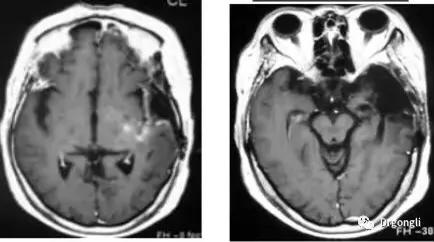

1) 惡性腦腫瘤的案例:

(來源:日本筑波大學)